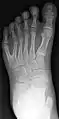

Radiographie de face du pied gauche d'un enfant atteint de polydactylie.